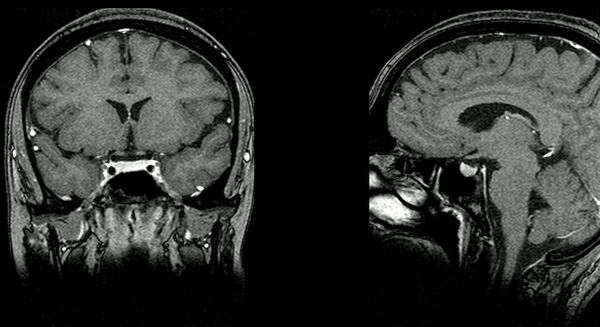

Гипофиз располагается в основании головного мозга (нижней поверхности) в гипофизарной ямке турецкого седла клиновидной кости черепа. Турецкое седло прикрыто отростком твёрдой оболочки головного мозга — диафрагмой седла, с отверстием в центре, через которое гипофиз соединён с воронкой гипоталамуса промежуточного мозга; посредством её гипофиз связан с серым бугром, расположенным на нижней стенке III желудочка. По бокам гипофиз окружён пещеристыми венозными синусами.

Размеры гипофиза достаточно индивидуальны: переднезадний/сагиттальный размер колеблется от 5 до 13 мм (до 16 мм у людей за 2 м ростом), верхненижний/корональный — от 6 до 8 мм, поперечный/аксиальный/трансверзальный — от 3 до 5 мм, масса гипофиза 0,5 г.